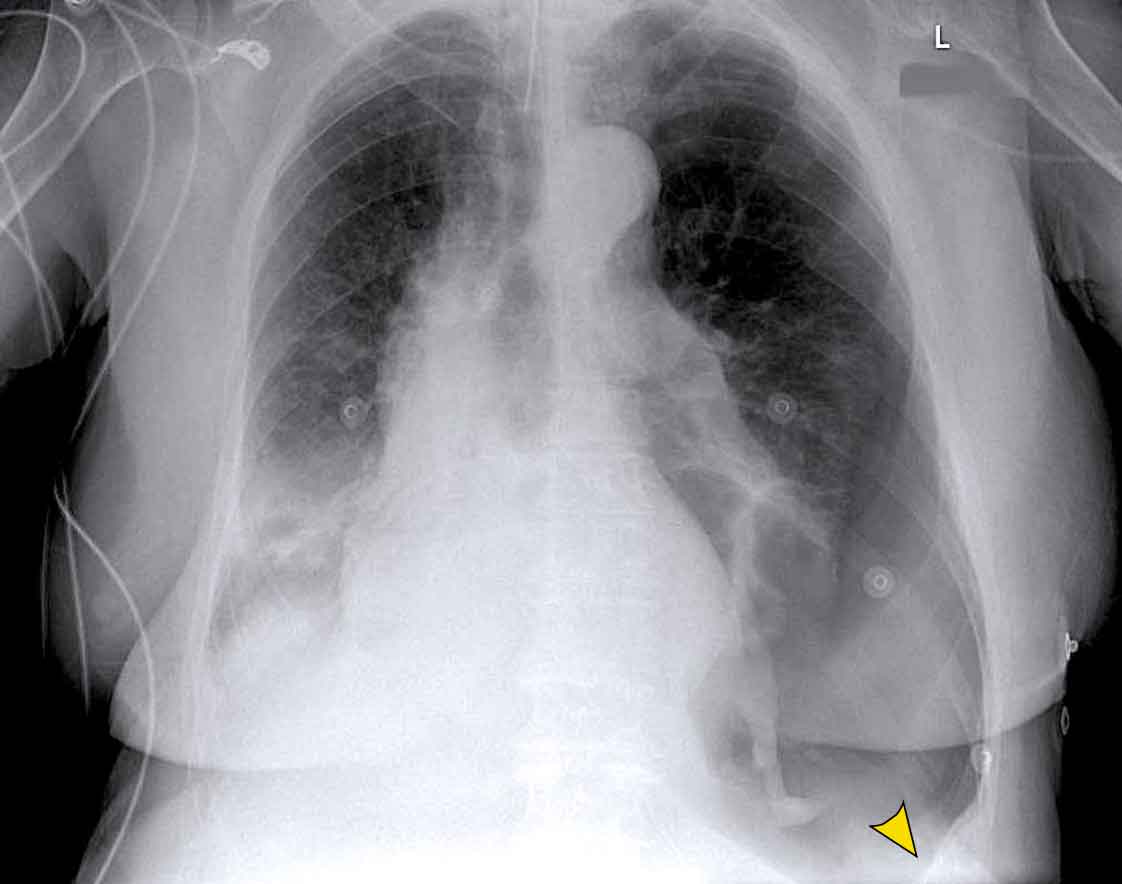

Case Example: Subtle Signs of Congestive Heart Failure

Begin by reviewing these current chest radiographs.

Based solely on these images, one might suspect congestive heart failure (CHF), though the findings are subtle.

Now review the previous study…

Scrolling between the current and prior films significantly increases diagnostic confidence in your diagnosis of congestive heart failure.

Key comparative findings include:

• Cardiac size: Slightly increased compared to the previous study; however, cardiomegaly was already present.

• Pulmonary vasculature: Mild vascular engorgement suggesting elevated pulmonary venous pressure.

• Interstitial markings: Subtle signs of interstitial edema .

• Pleural effusions: Bilateral small effusions, with subtle changes in the inferoposterior borders of the lower lobes, suggesting fluid accumulation.